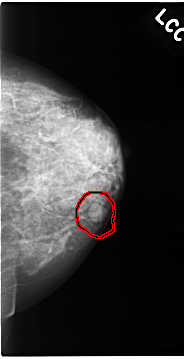

FILE: C_0064_1.LEFT_CC.OVERLAY

TOTAL_ABNORMALITIES 1

ABNORMALITY 1

LESION_TYPE MASS SHAPE OVAL MARGINS CIRCUMSCRIBED

ASSESSMENT 3

SUBTLETY 5

PATHOLOGY BENIGN

TOTAL_OUTLINES 1

BOUNDARY